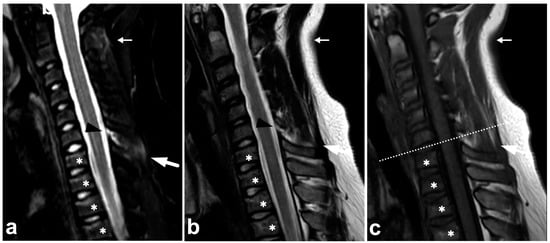

Figure 7.

(a) Sagittal left-sided off-midline T2-weighted. (b) Sagittal T2-weighted. (c) Sagittal right-sided off-midline T2-weighted. (d) Sagittal left-sided off-midline T1-weighted. (e) Coronal STIR. (f) Axial T2-weighted (dotted line on the image (c)). A 17-year-old female with a history of idiopathic juvenile scoliosis and acute spinal trauma due to a motorcycle accident. The patient had fractures and contusions in multiple vertebrae; the injuries in Th6, Th7, Th8, Th9, and Th10 (asterisks) are seen in the presented images. In addition to vertebral body fractures, the posterior elements were involved bilaterally in Th6 (arrows) and on the left side in Th7 (arrowhead). Facet joints remained congruent. Burst-like morphology is seen on the Th6 fracture. In image (b), the fracture seems to dislocate the spinal cord, but in the axial plane (not presented here), the cord was seen not to be compressed.